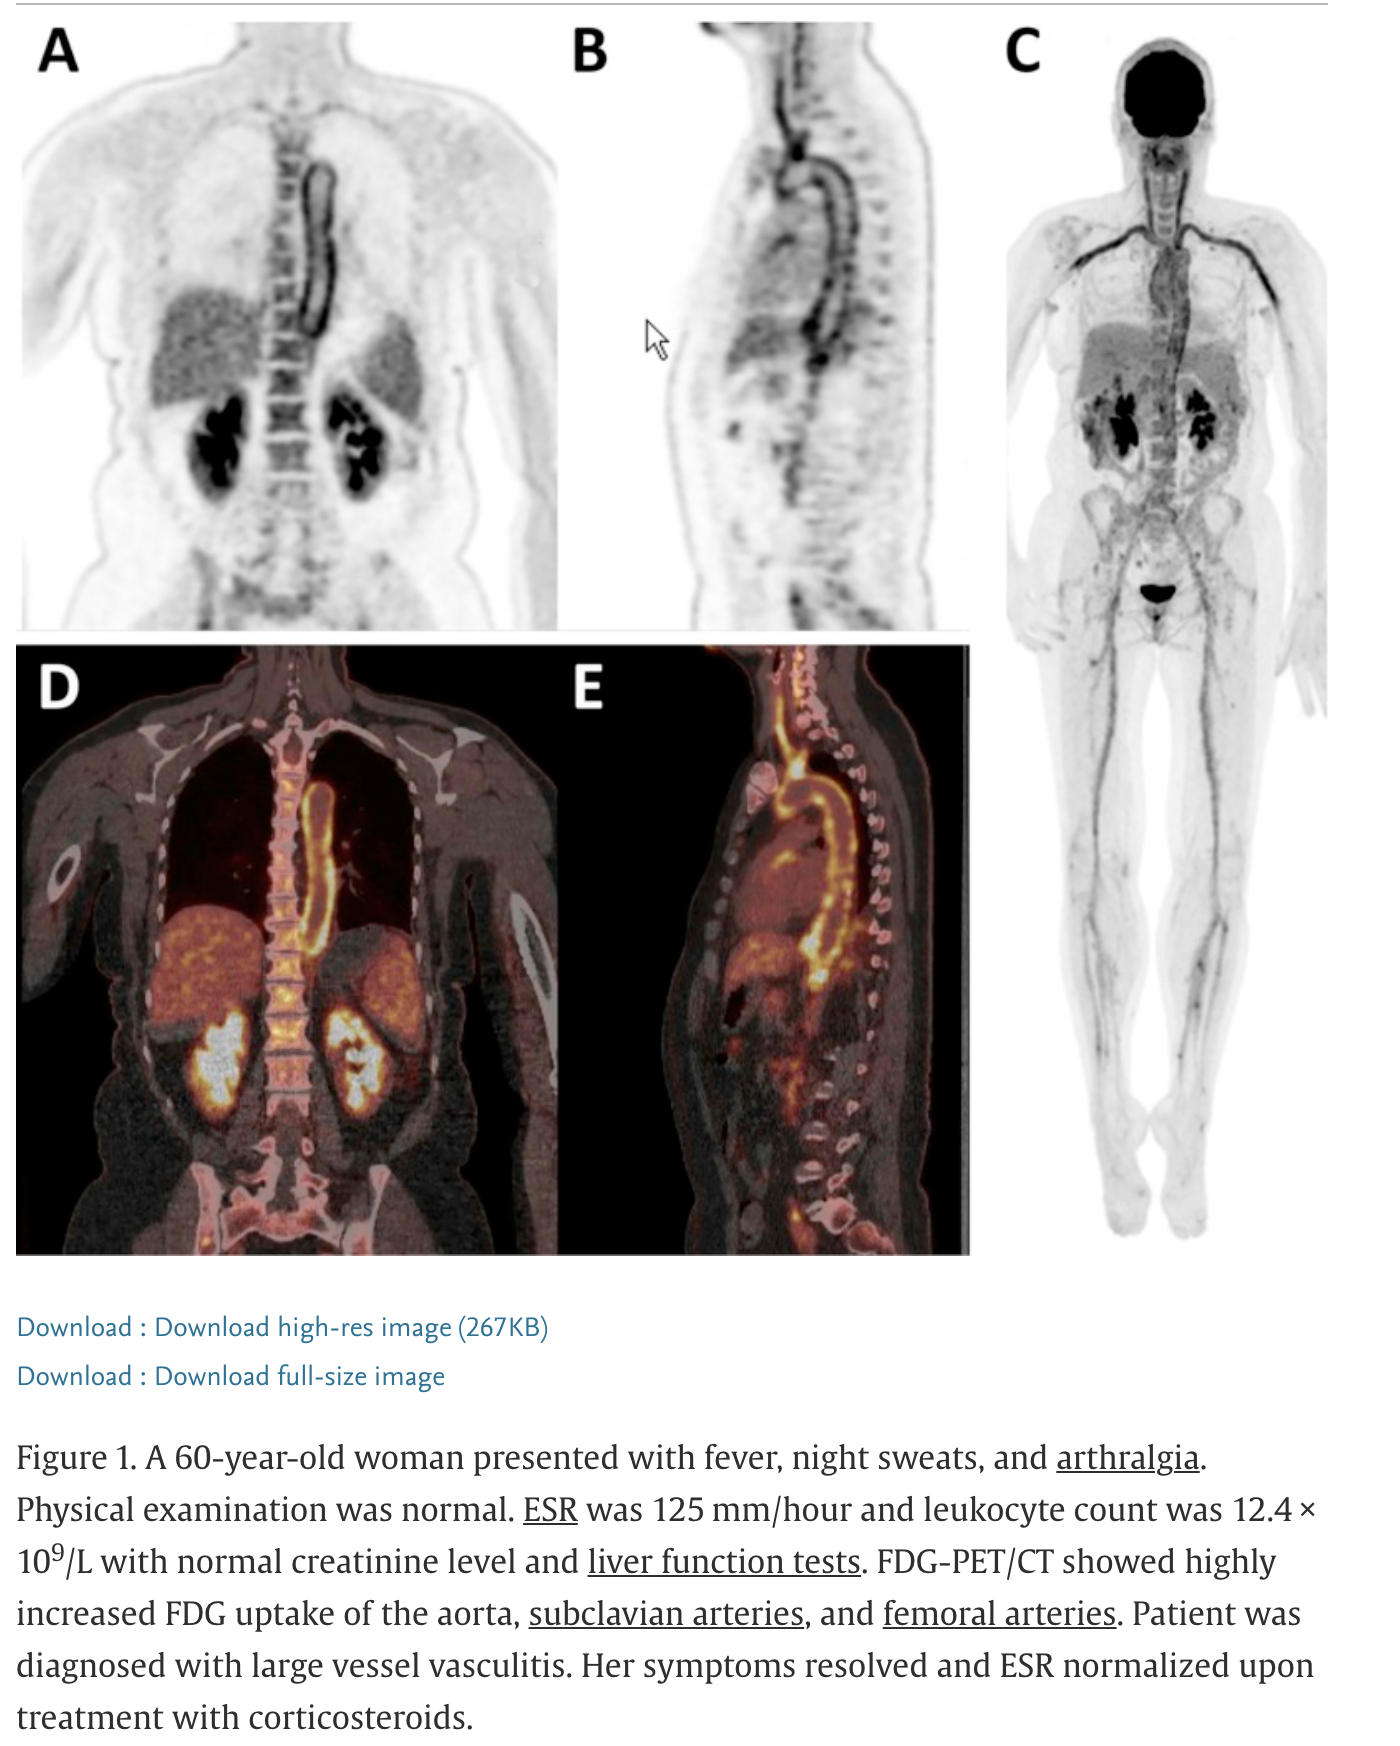

MRI for CNS, abdomen spleen and lymph nodes Aortic arch and proximal cervical arteries (vasculitis)